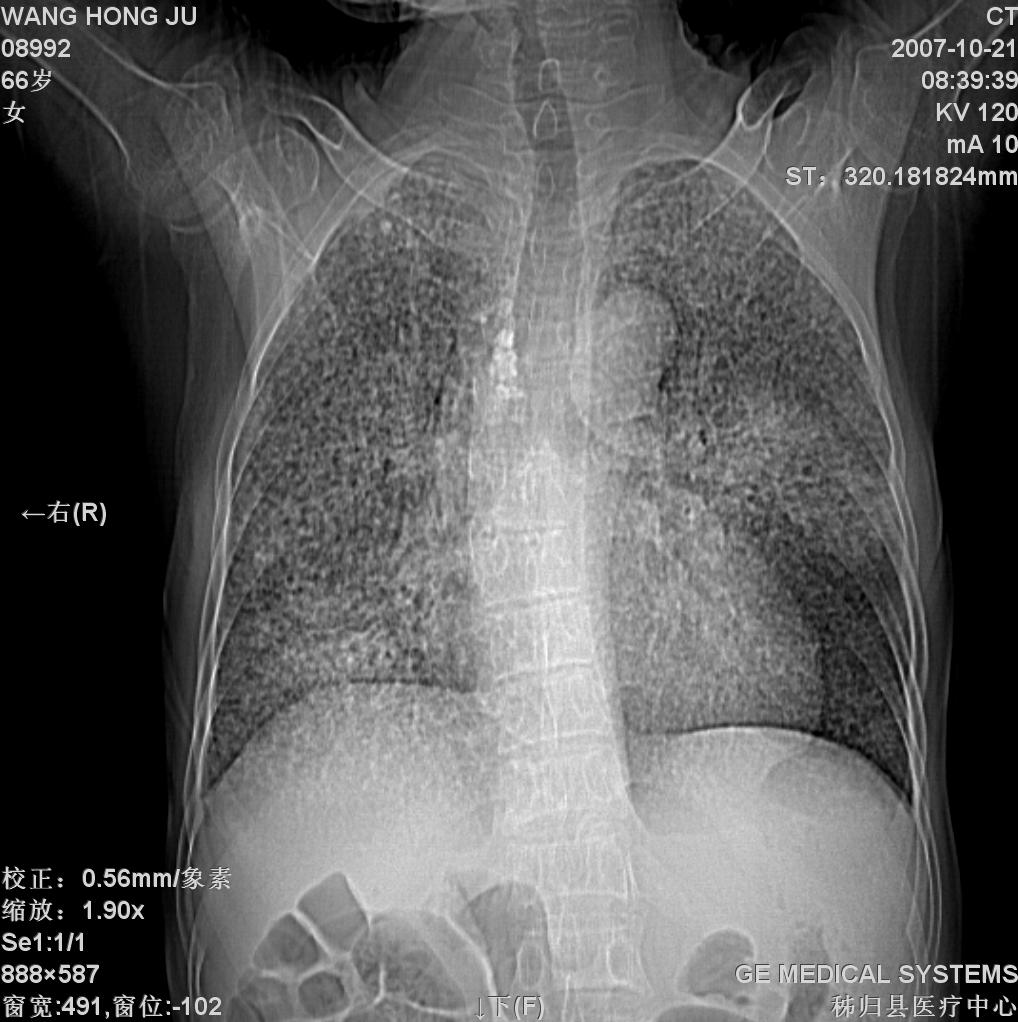

患者咳嗽月余,高热数天,咳黄色稍脓痰。

双肺野分布多个小结节状高密度影,其内散在斑片状模糊影,气管。支气管通畅,纵隔内淋巴结钙化,胸膜局限性增厚粘连,胸腔少量积液。结合病史考虑结核并感染的可能性大,胸膜炎并积液。肺泡癌待排。

纵隔内见钙化的淋巴节,上肺见钙化灶,双肺均匀弥漫分布小结节影,边缘较清楚,能不能考虑是在矽肺的基础上并发的结核和感染,请详细了解病史结合临床.